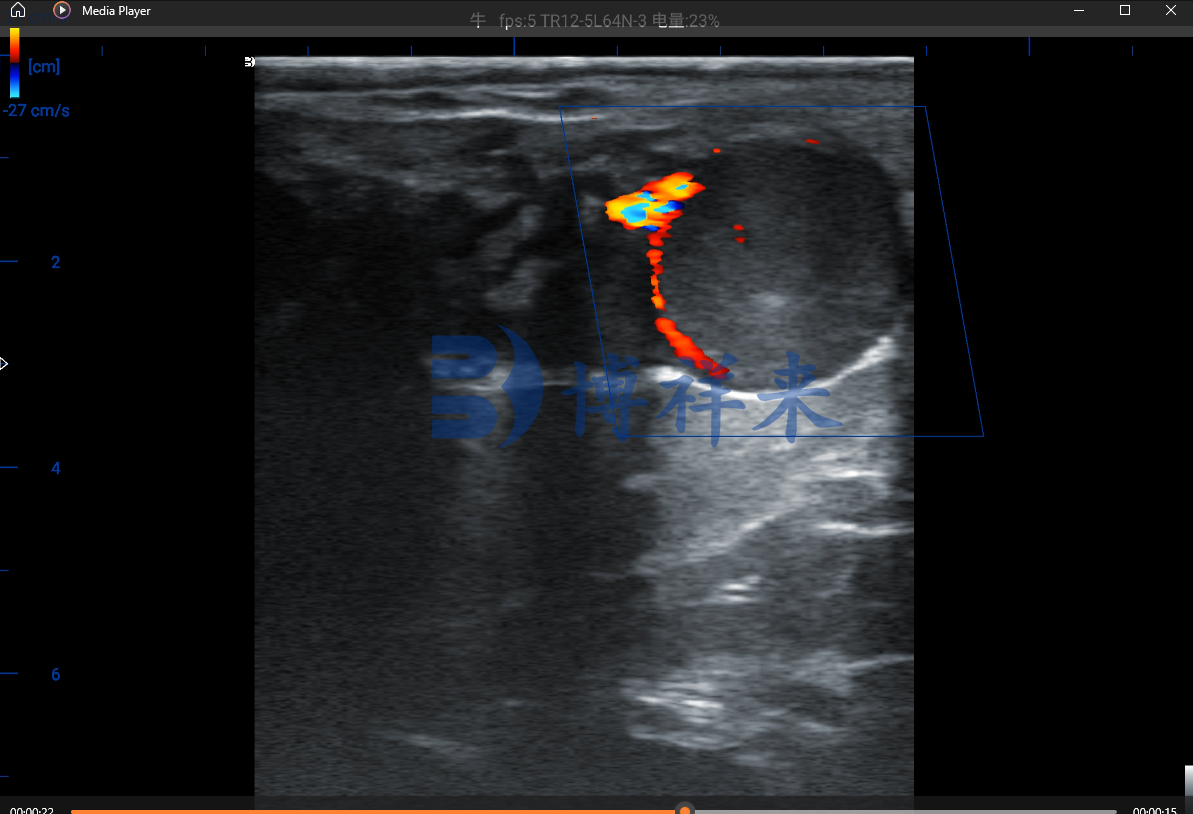

通过彩色/多普勒超声观察并记录卵巢上排卵侧(或两侧)黄体的血流:若黄体持续呈现丰富血流,且血流波形/阻力指标显示低阻(提示持续灌注),则高度提示妊娠;反之,血流显著减少或消失提示可能未妊娠或黄体正在退化。

阳性指征:黄体实质内或周边出现持续且明显的颜色流(color flow),肉眼可见红/蓝色信号表示血流。若色流丰富且分布均匀,提示黄体灌注良好,支持维持黄体功能,倾向妊娠。

阴性指征:黄体区血流微弱或不见色流,提示黄体正在退化,倾向非妊娠。

通过谱波可计算阻力指数(RI)、搏动指数(PI)、峰值流速(PSV)等参数。一般情况维持黄体的血供呈现低阻波形(较低RI/PI),而退化黄体波形呈高阻或无明显血流。